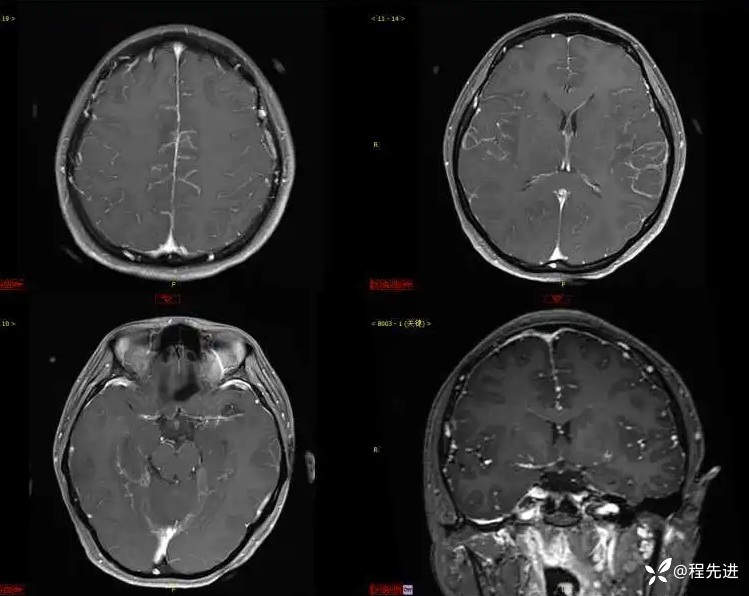

T1增强: